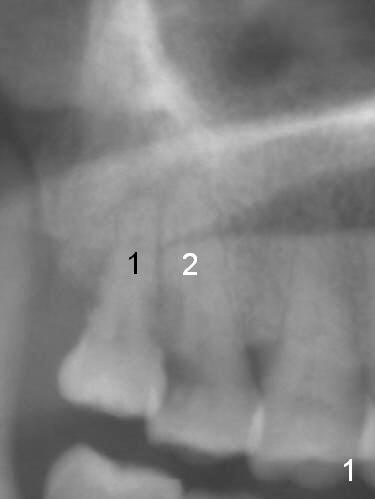

A 52-year-old woman presents to clinic with chief complaint "I can not bite in the upper right". Exam shows DO caries of the tooth #2 (Fig.1). After scaling & root planing and the tooth #1 extraction, pulpotomy is performed at #2. Two months later, pain recurs with swelling. When root canal therapy is finished at #2 (Fig.2-6), the tooth is found to have moderate mobility with guarded to poor prognosis. If the infection does not resolve, extraction and immediate implant seem to be necessary. Considering low bone density around the site of #2, a long implant is indicated (18 mm bone-level, Fig.7,8).